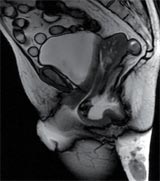

L’IRM pelvienne dynamique est une technique de plus en plus prescrite dans le bilan des troubles de la statique pelvienne (Illustration). Il faut dire que sa cotation est plus « attractive » que celle de la défécographie.

En bref, l’IRM pelvienne dynamique n’a pas fait aussi bien que la « bonne vieille » défécographie dans ce travail. Il faut dire que la position horizontale « antiphysiologique » des patients durant cet examen est un obstacle à l’étude des troubles de la statique pelvienne.